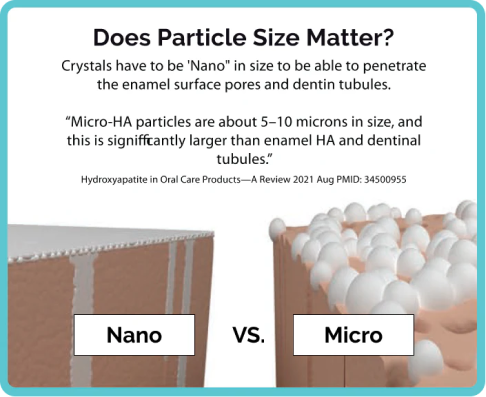

Formulated with 10% nano Hydroxyapatite, 0.22% fluoride, and Xylitol, Dr. Jen's Super Paste offers a powerful combination that strengthens enamel, fights cavities, and supports overall oral health.

Triple proven ingredients with 10% nano Hydroxyapatite, fluoride, xylitol